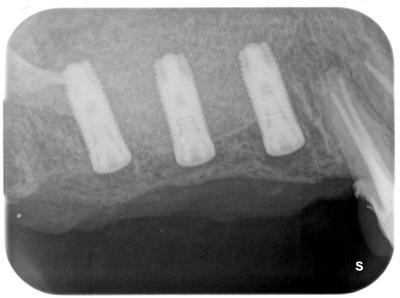

インプラント治療は、前医では骨がないから不可能と言われたらしいが、、、、、骨移植により、問題なく咬合回復できた。

サイナスリフト行いインプラント埋入時

金井_三千代_ライトボックス(1)_口腔内_20200829_100339.jpg